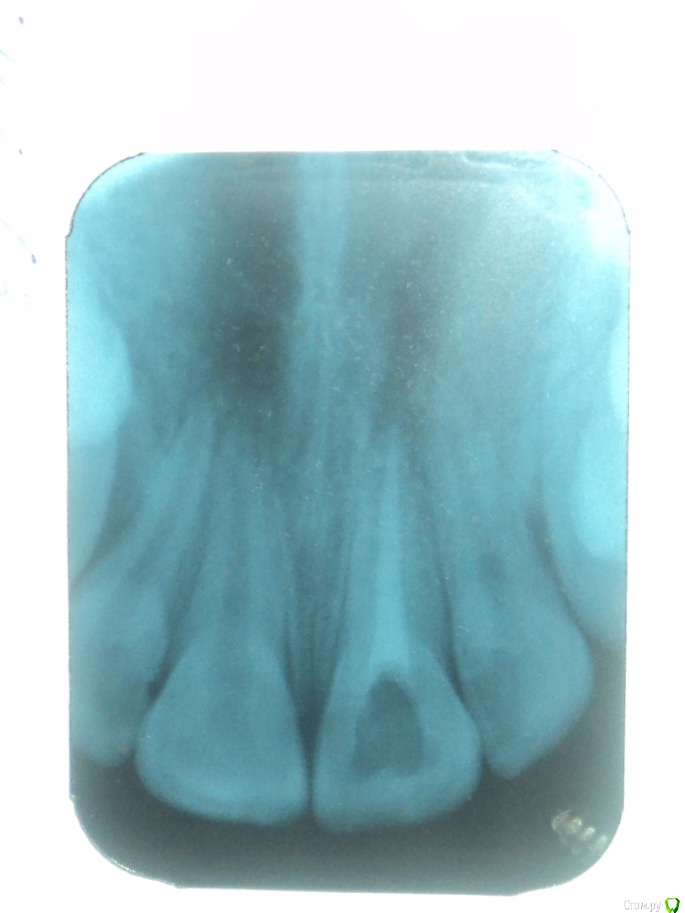

Здравствуйте! Примерно 12 лет назад у меня была травма переднего зуба после чего удалили нерв и  ввели в канал мне сказали метапекс, но по записям вроде не метапекс(фото с записями из карточки и снимки зуба прилагаю)  и запломбировали.  В течении примерно 10 лет (с 22.06.2005) этот зуб меня не беспокоил. Но в следствии ухудшения общего самочувствия я решил сходить к стоматологу. Мне сказали что у меня хронический периодонтит. У этого зуба посинела десна и это меня настораживает. Объясните мне в чем причина посинения десны? И я думаю что, то что происходит в этом зубе негативно сказывается на всем организме во первых как я думаю там может находиться очаг инфекции которая подрывает весь организм во вторых я почитал о действии на организм Метапекса( гидроокись кальция(гашеная известь)) и это действие очень не хорошее. Я не знаю что мне делать с этим зубом удалять или что то там менять чистить? Я не понимаю почему мне после стольких лет когда я пришел на прием мне ничего не сделали с этим зубом ничего не меняли и не чистили сказали все нормально и я ушел .так и должно быть? Жду ответа и совета врачей.

Удалять зуб не нужно. Снимок у Вас размытый получился, поэтому точнее сказать сложно. Посторайтесь либо перефотографировать снимок либо сделать новый.